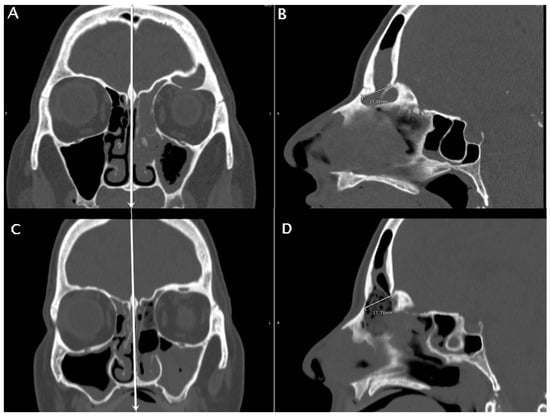

Figure 5.

A patient with fronto-ethmoidal inverted papilloma undergoing a DRAF III surgery. The pre-operative CT scan is in (A,B), the post-operative CT scan is in (C,D). Coronal sections are used to identify the mid-sagittal line by the location of nasal septum and crista galli (white vertical lines in (A,C)). The anteroposterior diameter of the frontal sinus ostium is then measured pre- and post-operatively on mid-sagittal sections (B,D). The anteroposterior diameter of the frontal sinus neo-ostium in the post-operatory mid-sagittal images (D) was termed the obtained diameter (OD).